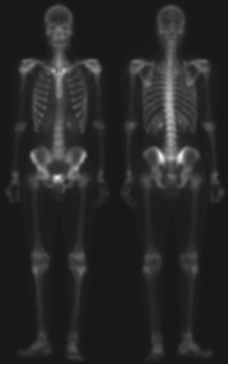

위의 사진은 뼈 감염이나 종양 같은 질환은 감지하는 전신 골격 원자력 스캔입니다. 디지털 영상 처리는 문제 지향형이기 때문에 어떤 문제를 가지느냐에 따라서 서로 다른 방향성을 가지게 됩니다. 저희는 사진에 있는 골격의 디테일을 살리는 것으로 하겠습니다. 지난 포스팅에서 따로 설명은 드리지 않았지만 라플라시안 필터는 영상의 세세한 디테일을 살리는 데 사용될 수 있으며 그래디언트 기반 필터링은 영상 내의 중요한 엣지를 찾아내는 데 도움을 줄 수 있습니다.

입력 영상 $I$에 라플라시안 필터를 적용하는 것은 라플라시안 필터를 이용한 영상 샤프닝의 시작이라고 하였습니다. 하지만 위의 그림을 보면 영상 내의 노이즈가 꽤 많이 있기 때문에 샤프닝된 영상은 노이즈가 많을 것이라고 예상할 수 있습니다.